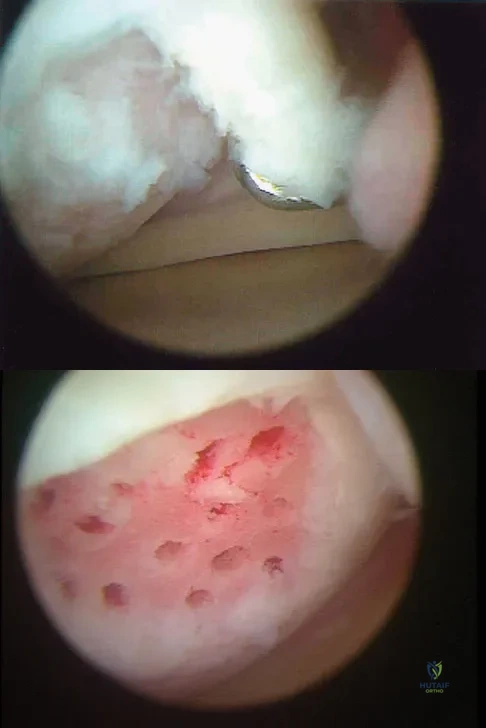

A 51-year-old male truck driver has had progressive left hip pain for more than 2 years, and he reports that the pain has become severe in the past 9 months. He is now unable to work because of the pain. Examination reveals that range of motion of the hip is limited to 95 degrees of flexion, 0 degrees of internal rotation, and 20 degrees of external rotation. The plain radiograph, MRI scan, and intraoperative gross photographs are shown in Figures 9a through 9d. Management should consist of

Explanation:

The diagnosis is synovial chondromatosis. While the plain radiograph fails to show any calcifications, the MRI scan shows an intra-articular mass that involves the capsule. Grossly multiple granular cartilage nodules are seen. Management should consist of removing all loose bodies along with the synovial membrane.